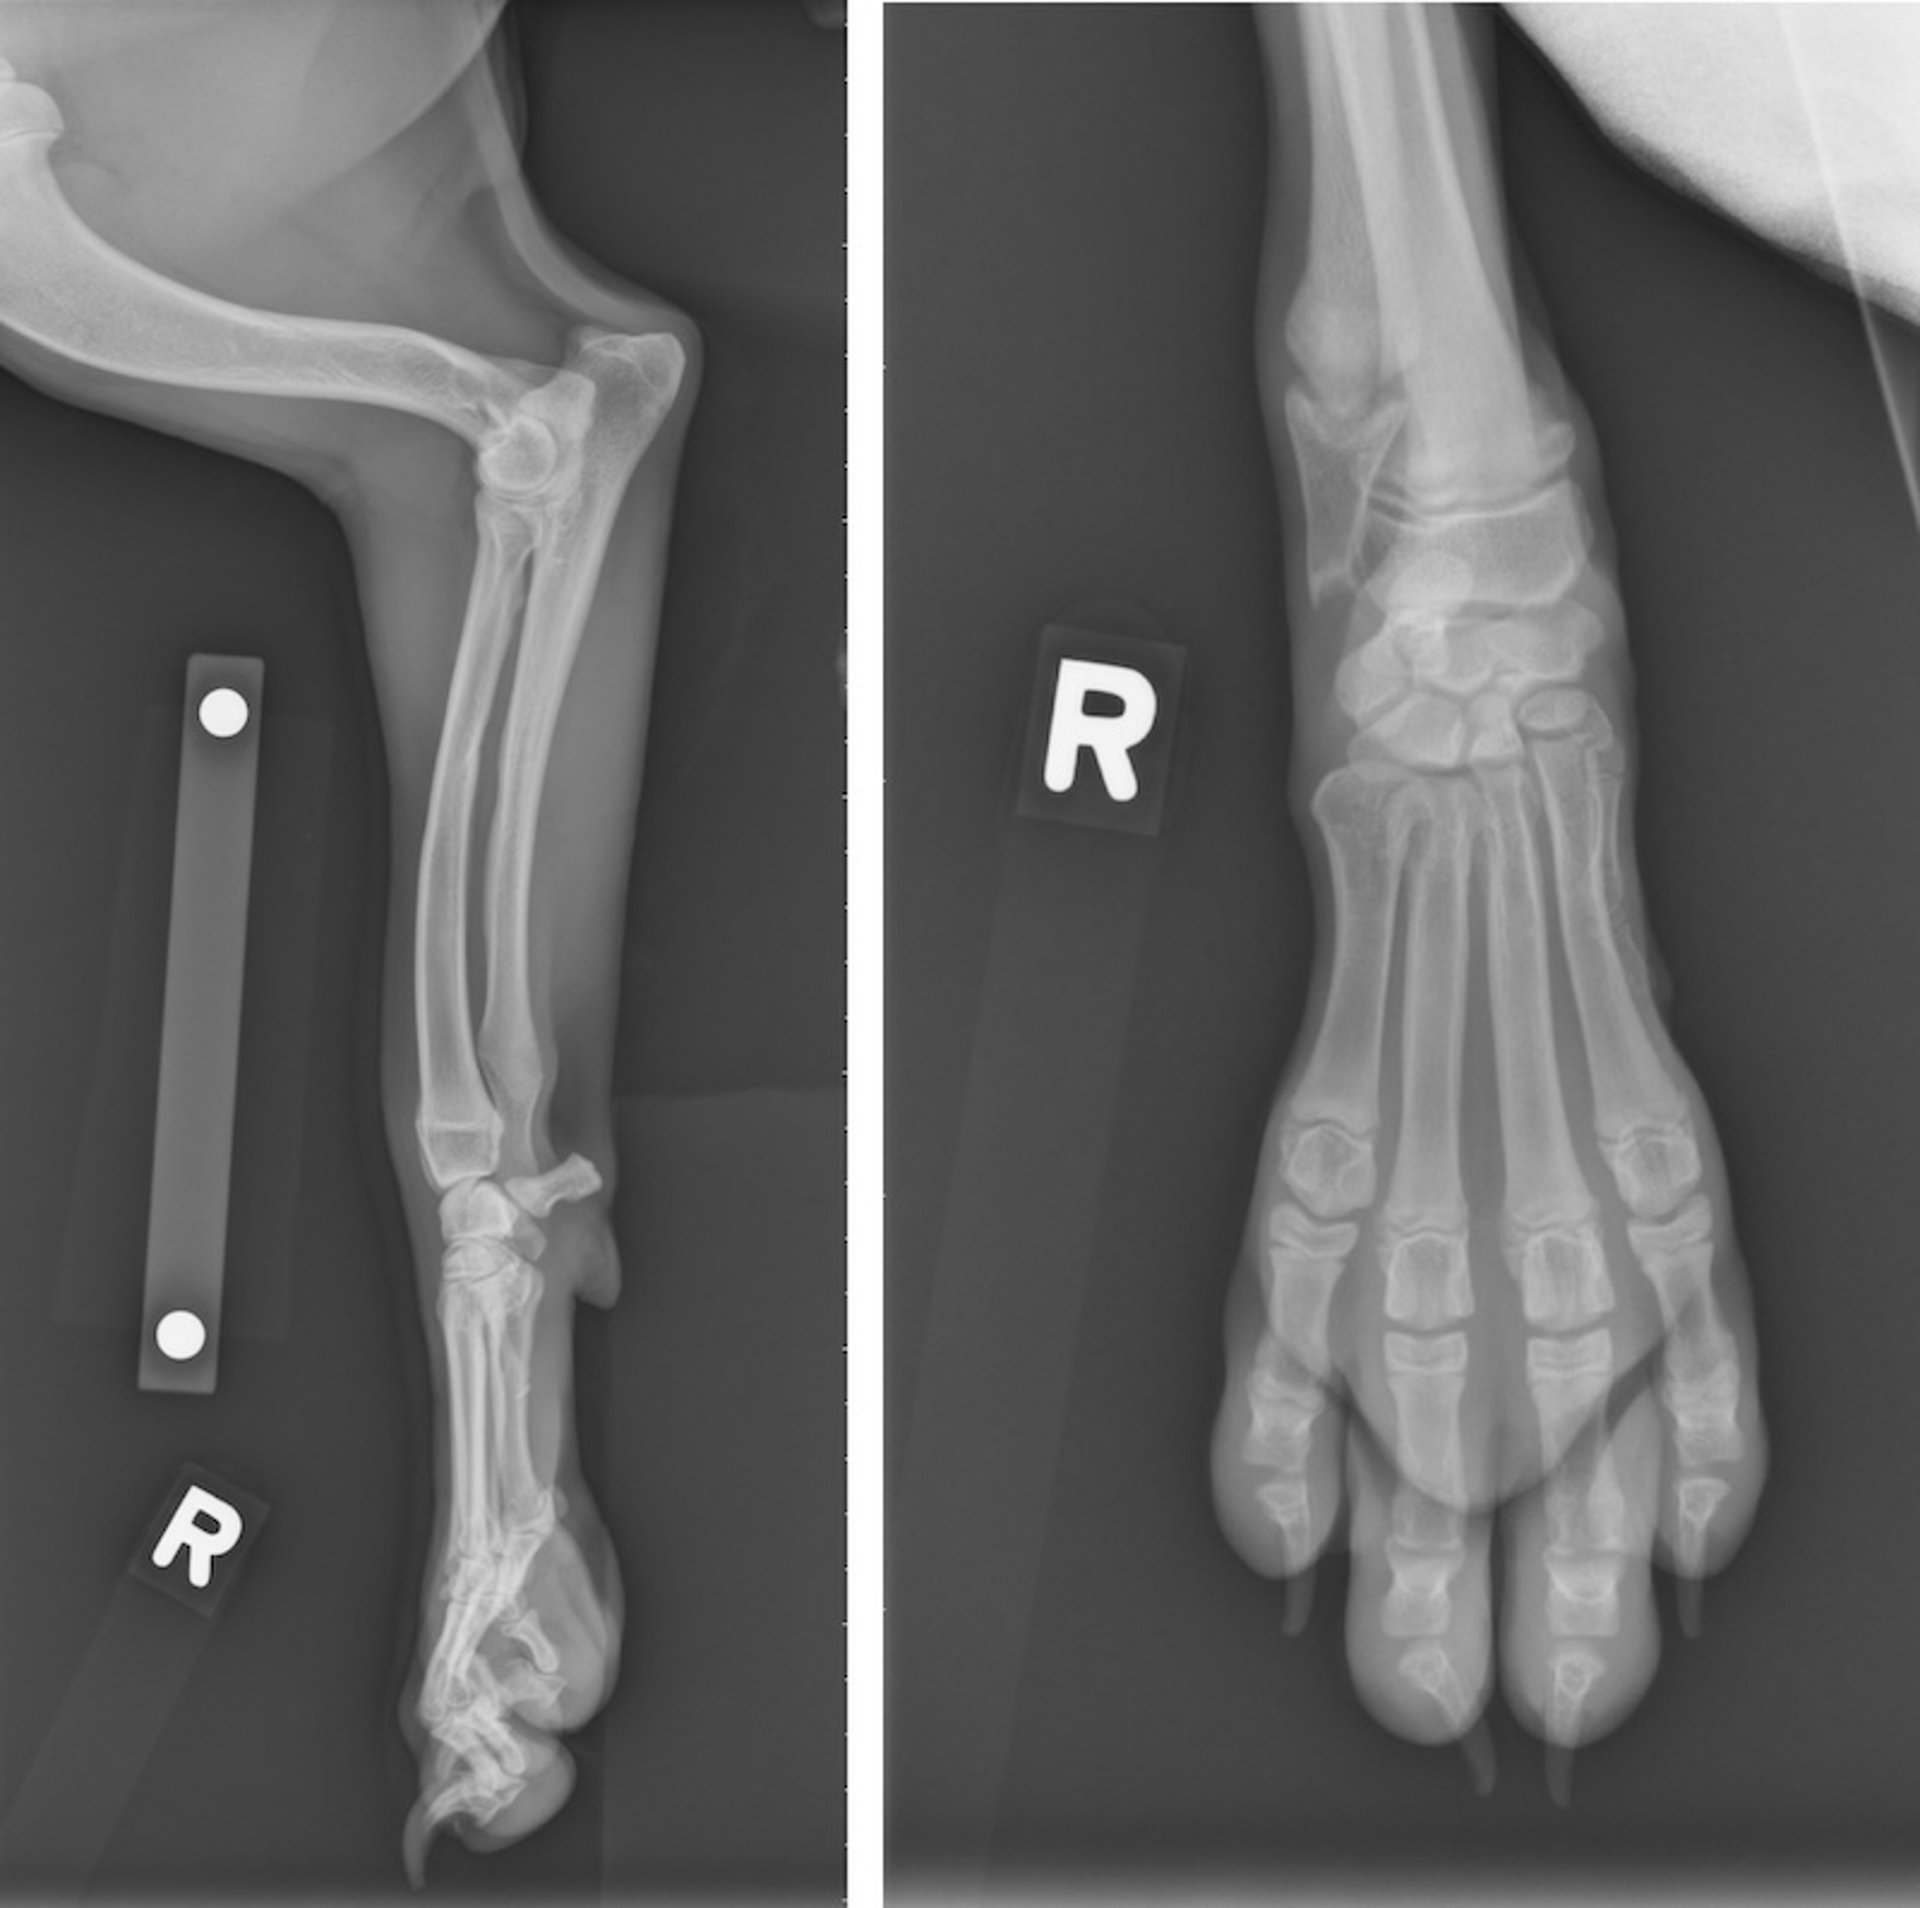

Hypertrophic osteodystrophy, radiographs, dog

Right carpal radiographs of a 3-month-old Boxer that developed fever, lethargy, and severe peripheral lymphadenopathy, along with swollen and painful paws. There is a paired radiopaque and radiolucent set of lines proximal to the distal radial physis. A less distinct radiodense line is associated with the distal ulnar physis. Soft tissue swelling extends from the distal radial and ulnar physes to encompass the manus.

Courtesy of Dr. Po-Yen Chou